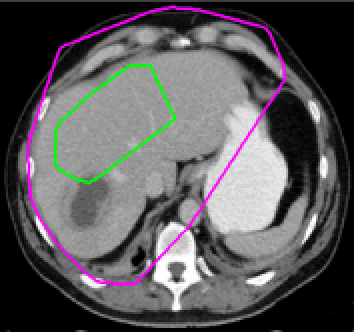

Four sets of test results are shown below. In Test 1 we compare models M1 – M6 to the proposed model M7 for two images which are hard to segment. The first is a CT scan from which we would like to segment the lower portion of the heart, the second is an MRI scan of a knee and we would like to segment the top of the Tibia. See Figure 9 for the test images and the marker sets used in the experiments. In Test 2 we will review the sensitivity of the proposed model to the main parameters. In Test 3 we will give several results achieved by the model using marker and anti-marker sets. In Test 4 we show the initialisation independence and marker independence of the Geodesic Model on real images.

Refer to captionRefer to captionRefer to captionRefer to caption

(i)                                 (ii)                                 (iii)                                 (iv)

Figure 9: Test 1 setting: (i) Image 1;  (ii) Image 1 with marker and anti-marker set shown in green and pink respectively;  (iii) Test Image 2; (iv) Image 2 with marker set shown.